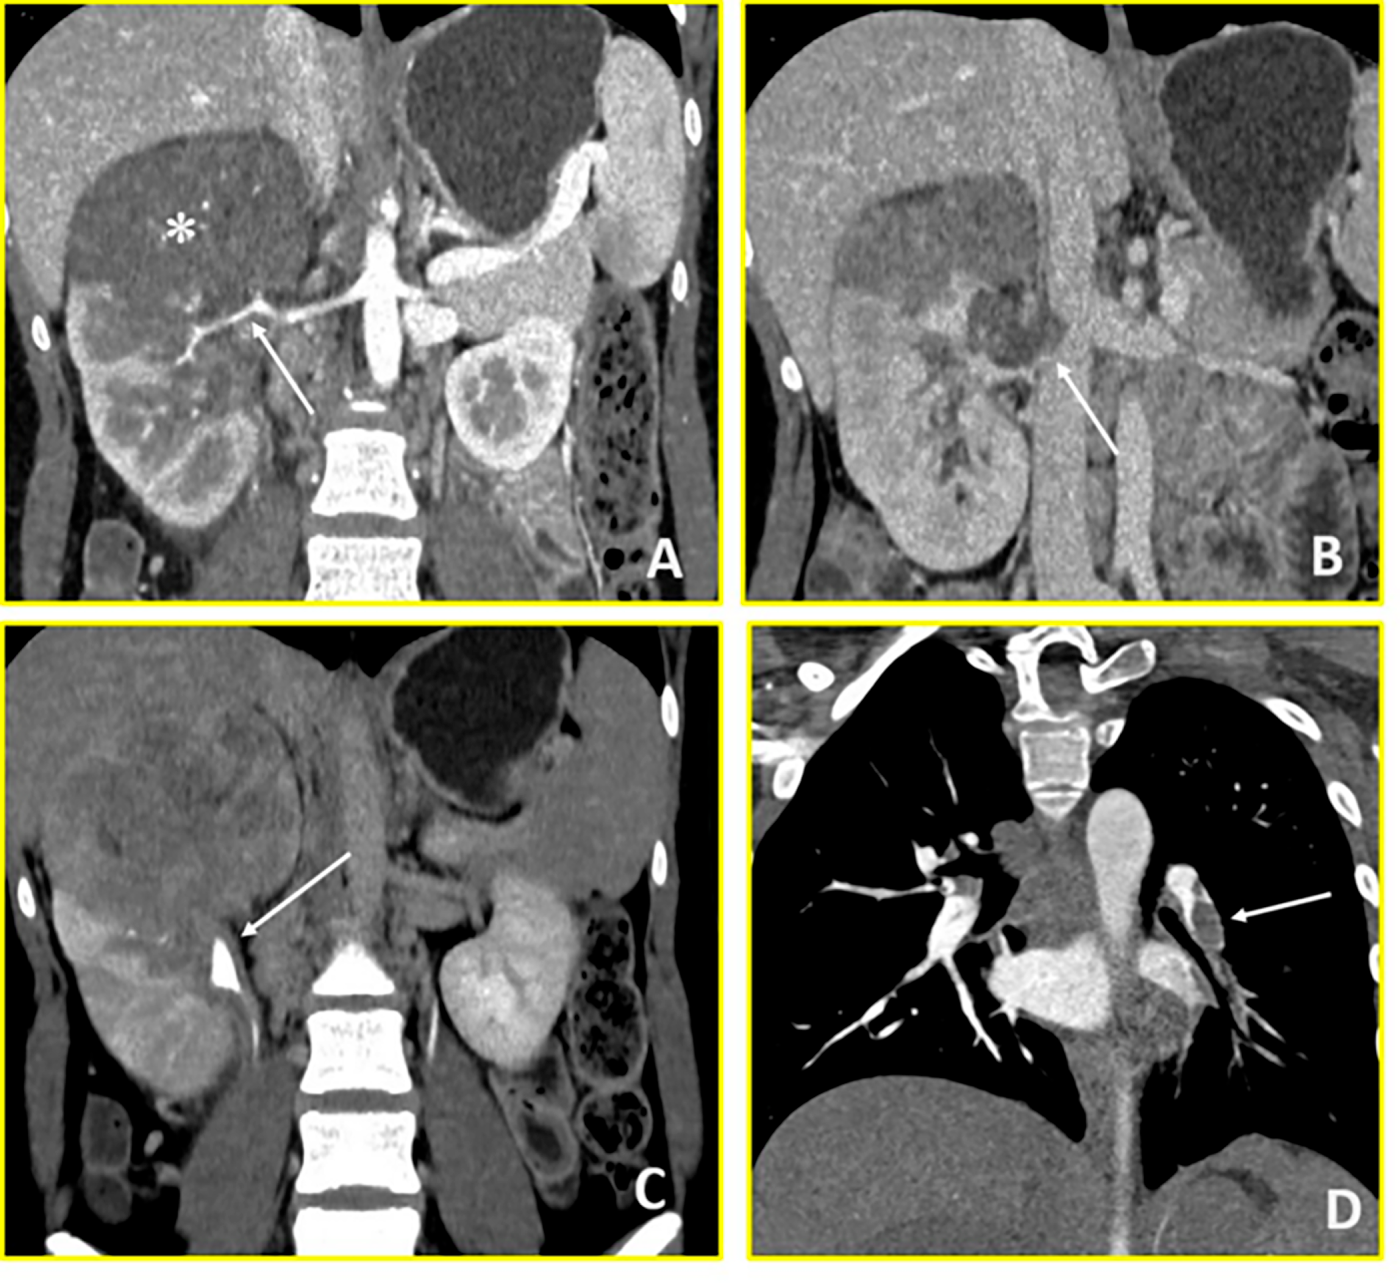

A 16-year-old female presented to Emergency Department of Policlinico Gemelli with abdominal pain and fever. Thoracic-abdominal CT revealed a large (83 × 80 × 96 mm) inhomogeneous mass at the right kidney’s upper pole with ipsilateral renal pelvis dilatation and right renal vein thrombosis extending into the inferior vena cava. Thoracic imaging scan demonstrated pulmonary thromboembolism with multiple pulmonary infarctions (Fig. 4). The clinical presentation was characterized by recurrent episodes of tachycardia (heart rate > 120 beats per minute). Urgent transesophageal echocardiography was performed, revealing a hyperechoic filamentous formation measuring approximately 2.5 cm, widely mobile from the inferior vena cava, projecting into the right atrium to the tricuspid valve plane. The marked mobility of this atrial thrombus, observed even with patient movements during the examination, indicated extremely high risk of catastrophic embolization or acute right ventricular outflow obstruction. Basal abdominal MRI imaging examination was not possible due to the rapid evolution of the clinical picture. An urgent multidisciplinary discussion involving urologist, cardiac surgeon, anaesthetist, radiologist and oncologist led, due to the condition of haemodynamic instability and the risk of immediate thrombus rupture, to immediate cavectomy, thrombus removal and open right radical nephroureterectomy. Intraoperatively, the patient experienced cardiac arrest requiring cardiopulmonary resuscitation and pharmacological intervention. Post-operative thoracic CT demonstrated massive pulmonary embolism necessitating emergent pulmonary artery thrombectomy. The patient was managed in the Cardiac Intensive Care Unit with continuous intravenous heparin anticoagulation. Once stabilized, she was transferred to the Paediatric Oncology Department on postoperative day one. Histopathological examination with molecular testing confirmed Wilms’ tumour with a biphasic pattern. Following resolution of thromboembolic complications, high-risk post-operatory chemotherapy was initiated according to the SIOP-Umbrella 2016 protocol, alternating Cyclophosphamide/Doxorubicin and Carboplatin/Etoposide courses. Radiotherapy was delivered at week 10 (15 Gy to lungs, 25.2 Gy to tumour bed). End-of-treatment imaging showed complete remission, and the patient remains disease-free at one-year follow-up. In this initial phase of monitoring, her follow-up includes clinical examinations, blood tests, abdominal ultrasound scans and chest X-rays every three months.

Figure 4: Wilms’ Tumour (Case 4). Contrast-enhanced CT imaging demonstrates a hypovascular right renal mass with vascular invasion and distant thrombotic complications. (A) Coronal arterial-phase image reveals a predominantly hypovascular mass in the right kidney (asterisk) with infiltration of the right renal artery (arrow). (B) Coronal venous-phase image shows tumor thrombus in the right renal vein with extension into the inferior vena cava (arrow). (C) Coronal urographic-phase image demonstrates infiltration of the renal collecting system with involvement of the calyces (arrow). (D) Coronal arterial-phase image of the chest reveals a filling defect in the left interlobar pulmonary artery (arrow), consistent with pulmonary thromboembolism.